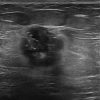

Ung thư vú

Ung thư vú - Ảnh 4

» Thông tin: Nữ giới – 51 tuổi.

» Lâm sàng: Khối tuyến vú.